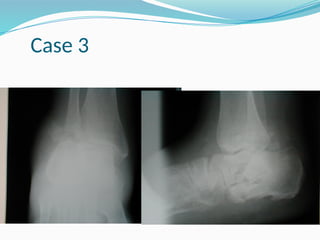

Case 3

DNOAP III Ulceration overthe navicular Verticalisation of the talus Navicular subluxation Destruction of talonavicular articultaion

• 86.